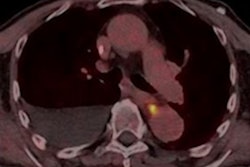

Performing PET/CT scans while patients are undergoing radiotherapy prior to surgery for esophageal cancer can help predict whether they will respond to treatment, according to a study published April 18 in Radiotherapy and Oncology.

South Korean researchers analyzed data from PET/CT scans in patients with esophageal cancer who underwent imaging about midway through radiotherapy treatment prior to surgery. They found that specific PET/CT parameters predicted how long patients survived without their cancer reappearing.

Metabolic parameters evaluated by F-18 FDG-PET/CT are known prognostic markers in various cancers. In the current study, the South Korean researchers hypothesized that measuring these parameters in patients with esophageal cancer midway through radiotherapy could predict their overall treatment response.

The researchers included 83 patients in the study who were treated with radiotherapy with or without chemotherapy and who underwent mid-therapy F-18 FDG PET/CT scans (Biograph TruePoint 40, Siemens Healthineers) between 2015 and 2020.

Among the PET parameters, the strongest statistically significant finding was the correlation between higher midradiotherapy SUVmax and locoregional recurrence (p = 0.009), according to the findings. In addition, the researcher found that a cutoff value of 11 for midradiotherapy SUVmax successfully distinguished between poor and better prognosis, the researchers stated.